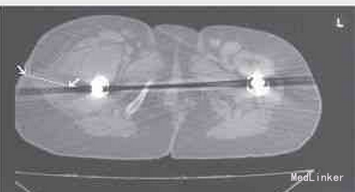

可能由于感染并髋臼松动,该病例初步诊断为全髋关节置换术后失败。患者于30年前行双侧初次Howse全髋关节置换术,并于11年前因无菌性松动而翻修。应用陶瓷假体替换原先的髋臼假体,之后因失败于1999年再次翻修。此次应用Burch-Schneider强化钛网架来翻修髋臼,股骨假体改用Muller钛柄。第二次翻修手术期间,在右侧髋关节周围发现大量肉芽组织。遗憾的是,当时并未对这些组织进行病理学检查。 在手术瘢痕周围的结节病灶区内,取三处不同部位组织进行病理学检查。由四位病理学家对标本进行病理分析,诊断为血管肉瘤。CD31、CD34和Fli-1的免疫组化染色结果也证实了这一诊断。 胸腹部计算机断层扫描结果显示,在其肺部存在一些与肿瘤转移灶特征不一致的结节性病灶,报告为慢性炎性改变同位素骨扫描显示双肩均有核素浓聚增加,与骨关节炎性改变一致。 骨盆磁共振成像扫描显示,在松动的右侧髋关节周围有大的软组织团块,且该团块侵及皮肤(图3)和腹股沟淋巴结。半侧骨盆切除术曾被认为是唯一适合的手术方式,但基于对皮肤病灶的检查及扫描影像的评估,认为无法将肿瘤组织完全清除。患者年龄和身体条件意味着无法耐受如此广泛的切除手术。同时患者本人已接受所患的疾病不能治愈且生存期有限,因此不希望接受进一步的大手术。